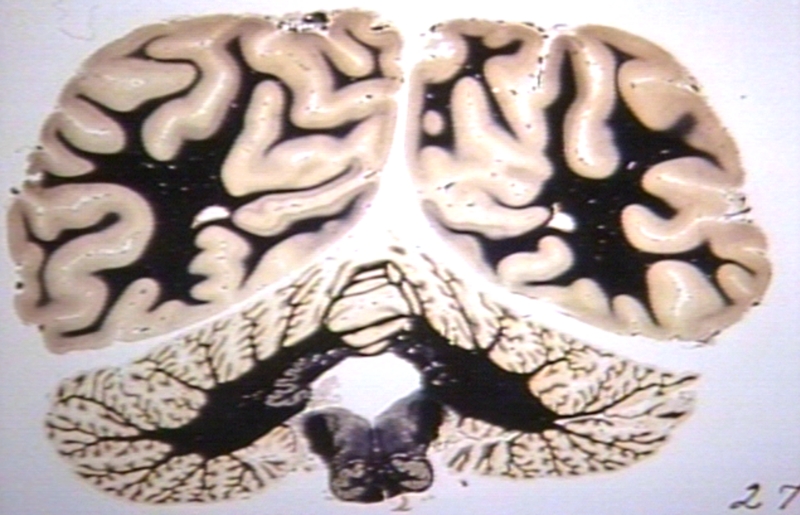

HISTOLOGY: NERVOUS: BRAIN: BRAIN ATLAS, MEDULLA; AFIP ATLAS